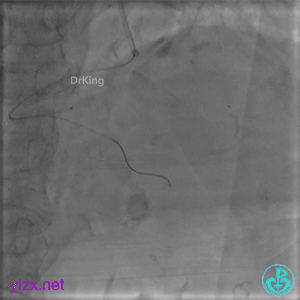

远段造影剂外渗在增加,怎么办?

微导管送入PL分支远段,取明胶海绵颗粒栓塞剂1ml通过微导管向远端血管推注栓塞远端血管。

封堵后造影,PL分支远端血流中断。